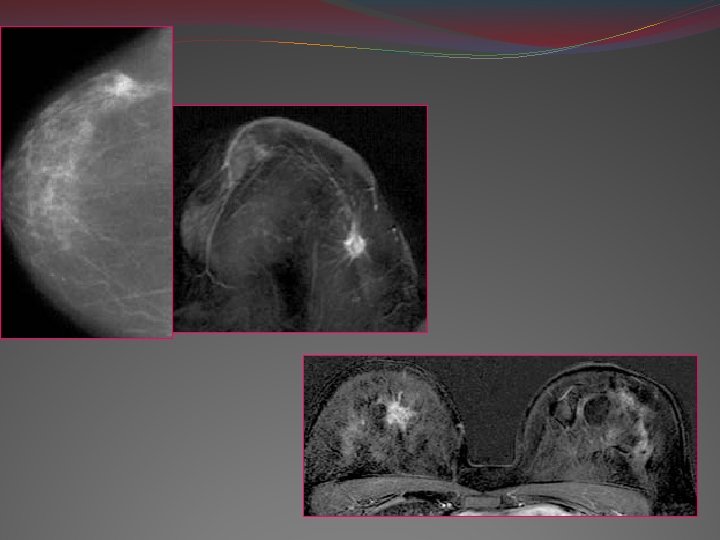

3 -IRM mammaire: • Examen de 3ème intention • Obtention de coupes fines dans tous les plans de l’espace • Exploration en même temps des régions axillaires et pré thoraciques TECHNIQUE: • Procubitus • 0, 5 -1, 5 Tesla • Antenne de surface : bi- sein, avec système de compression • J 4 -J 15 +++

• Plan axial+++ • Coupes fines en HR <4 mm • Séquences: en écho de spin mais mieux écho de gradient • T 2, T 1 +/- FAT SAT • -Gado/ +Gado : injection dynamique (1’, 3’, 5’) • Soustraction

• Étude de la courbe de rehaussement Rehaussement physiologique non masquant: normal Non précoce, lent et faible (< à celui de la graisse)

INDICATIONS DE L’IRM: 1 -Détection: Risque très élevé/risque génétique + seins denses ou prothèses mammaires Recherche d’un primitif mammaire avec mammographie nle 2 -Caractérisation: Distorsion architecturale ou image sur une seule incidence ou incertitude de diagnostic 3 -multi focalité / multi centricité/ bilatéralité CONTRE INDICATIONS ++

IRM: Morphologie: lésion à contours spiculés Rehaussement localisé, précoce, rapide et intense +++

Recherche de multicentricité/ multifocalité

Atteinte synchrone Atteinte multi focale / Atteinte multi centrique

1: centre de la tumeur (cellules tumorales) 2: périphérie de la tumeur (angiogenèse) Courbe de la cinétique du rehaussement du signal de la tumeur et du wash out

IRM mammaire: multicentricité, multifocalité, bilatéralité extension au plan pectoral+++ Autres moyens: extension ganglionnaire PET par FDG lympho scintigraphique isotopique Bilan d’extension à distance: Rx thoracique Échographie abdominale Scanner cérébral Scintigraphie osseuse, PET scanner classification TNM